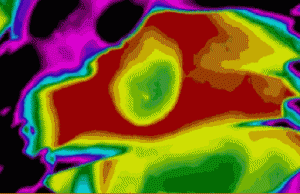

隨后,研究人員開(kāi)始在活體動(dòng)物身上進(jìn)行對(duì)照實(shí)驗(yàn):他們?yōu)樾∈筮M(jìn)行了開(kāi)胸手術(shù),人為阻斷心臟血液供給來(lái)模擬心臟病發(fā)時(shí)的狀況。此時(shí),再將藻類注入小鼠心臟并進(jìn)行光照,效果是顯著的,藻類產(chǎn)生的氧氣馬上被缺氧的心肌細(xì)胞吸收。

只過(guò)了僅僅?10 分鐘,在光照環(huán)境中的心臟部分的氧氣就增加了?25 倍,而與之對(duì)應(yīng)的仍處于黑暗環(huán)境中的心臟部分的氧氣只增加了?3 倍。

45 分鐘左右,拿只接受光照但沒(méi)注入藻類與只注入藻類但沒(méi)接受光照的心臟進(jìn)行相比,同時(shí)接受藻類和光照的小鼠心臟的供血量分別增加了60%和30%。